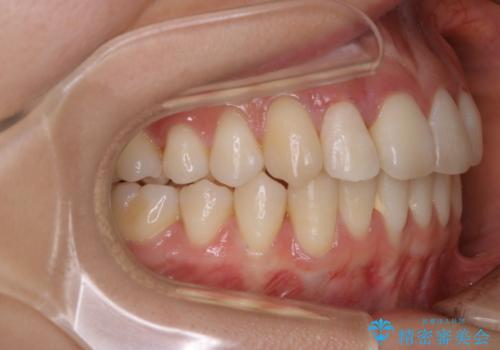

非抜歯でも劇的変化 インビザライン矯正治療

- 前歯のガタつきと噛み合わせの改善を主訴に初診来院され、審査の結果マウスピース装置による非抜歯での矯正を行うこととなりました。

元々の顎骨や口腔・歯槽骨が小さく、どうしても歯が並びきらない状況になっていました。マイクロインプラントという固定源からゴムかけを行うなど、補助装置を活用しながら臼歯部を順番に遠心方向(奥)に移動させていくことで抜歯をしなくても歯が並ぶよう計画を立てました。

歯のガタつきを治すため矯正治療を希望。審査の結果、非抜歯での矯正が可能であるという見通しが立ったためインビザラインによる非抜歯矯正治療を行った。

歯を並べるスペースを作るために、歯の遠心移動と歯列の拡大、歯自体を少しだけ小さく削る(IPR)という方法を複合的に組み合わせて配列を行いました。遠心移動用のゴムかけにはマイクロインプラントという小さいネジを用いて骨に直接固定源を求めました。